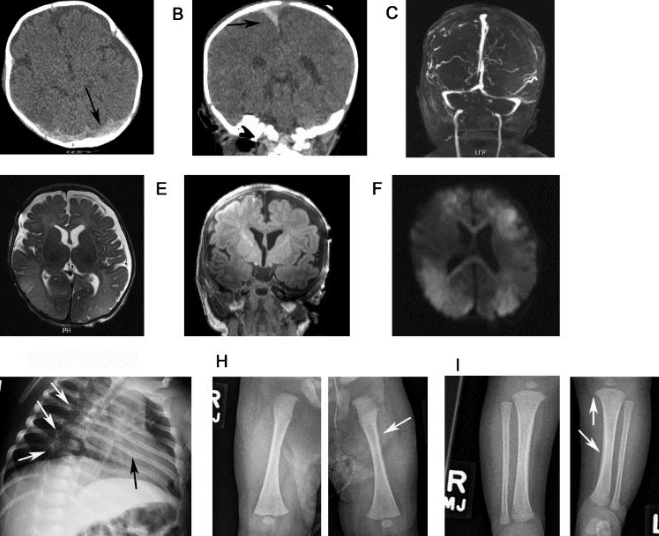

NAI: Head & Viscera - Beyond Broken Bones

• Abusive Head Trauma (AHT): Critical intracranial injuries.

• Subdural Hematoma (SDH): Interhemispheric, convexity, posterior fossa; often thin.

• Retinal Hemorrhages: Highly specific; often bilateral, multilayered, extending to ora serrata.

• Hypoxic-Ischemic Injury (HII): From shaking/impact; diffuse cerebral edema, watershed infarcts.

• AHT Imaging:

-   CT for acute bleeds; MRI for subacute/chronic changes, HII, and small SDHs.

• Posterior rib fractures, especially multiple and healing, strongly indicate abuse.

• Subdural hematomas (SDH), particularly interhemispheric, are common in abusive head trauma.

• Retinal hemorrhages are strongly associated with abusive head trauma.

• CT head for acute injury; MRI for detailed brain assessment and timing of injury.